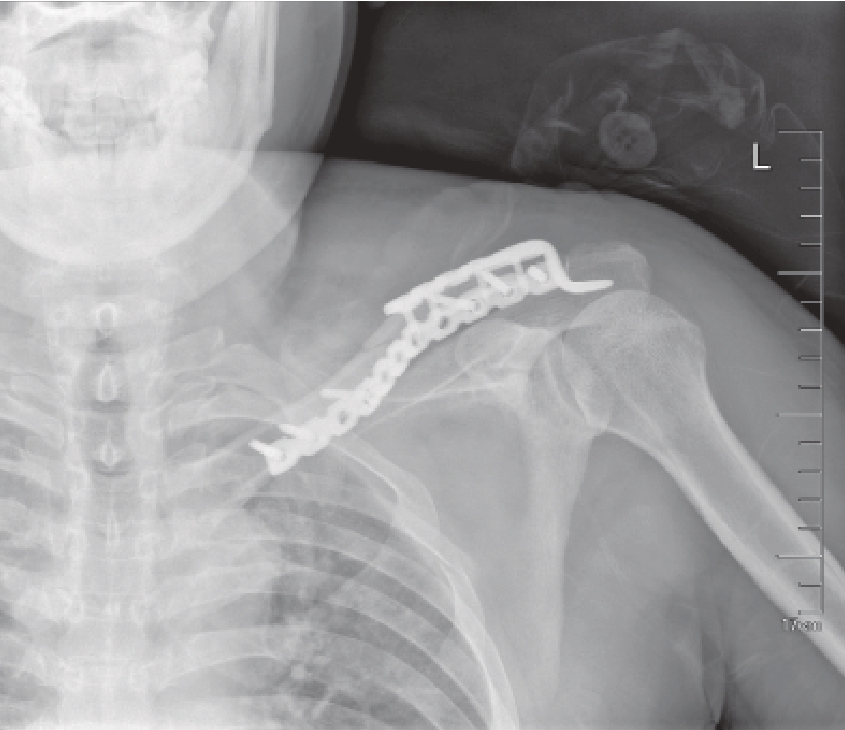

图1—15 中段锁定钢板+远端锁骨钩钢板固定

img